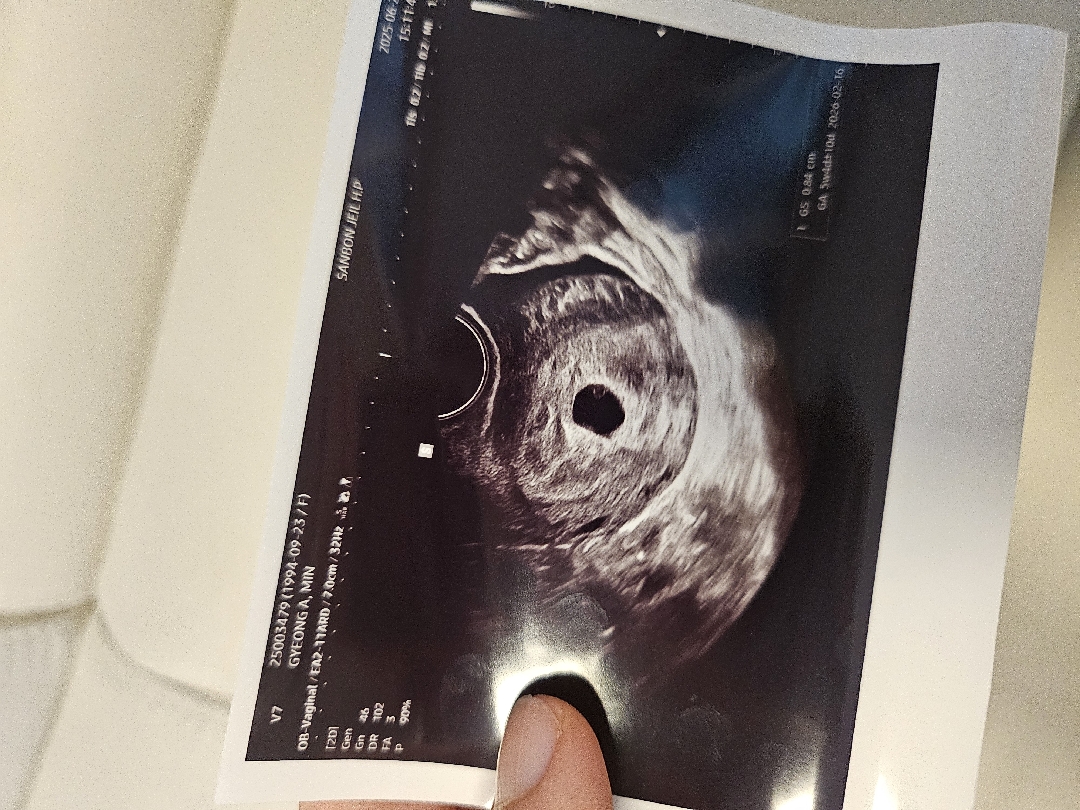

임신 소식을 알고부터 같은 주수되는 분들 후기를 아주 많이 찾게 되는 1인으로서 도움이되실까해서 후기 남겨봅니다 *막생 : 5/15 *임테기 두 줄 확인 : 6/9 *산부인과 방문 : 6/20 (막생 기준 5주1일차) 6월 9일쯔음 확인하고 임테기로 잘 자라고있나 연명하다가 5주 1일째 되는 오늘, 드디어 다녀왔어요! 막생 기준으로 5주1일째인데 아기집 크기봤을따는 5주 4일째고 출산예정일은 네이버계산기(2026.02.19)보다 3일 이른 2월 16일이더라구요 난황 아기집 모두 확인했고 2주 후에 심장소리 들으러가기루햇어요~

저도 막생 같은데 19일에 병원다녀왔거든요 ㅠㅠ..! 배로는 안보여서 질촘파로 보고왔는데 아기집이 진짜 새끼손톱만해요 난황도 안보이고... 다른 주차 분들보다 아기집이 너무 작아서... 걱정이에요... 요이님 곧 보이실거에요!